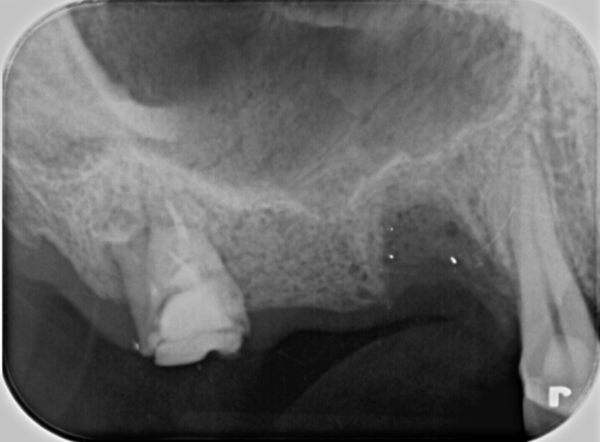

患者様は20代の女性。右下5番目の歯の中心結節という歯の一部が破折してしまったことで痛みを感じて来院された症例です。

痛みの原因は、歯髄腔(神経の部屋)まで到達した破折から感染を起こしてしまったためでした。このためレントゲンでみると歯の根先部には、小指大の大きさの黒い透過像があり、ここに炎症の際に出る膿などが溜まり根尖病変が確認されました。

当院でマイクロスコープ(歯科用顕微鏡)を用いて感染根管治療を行い、根っこの先までお薬で緊密に封鎖しました。

治療後、痛みも治まり噛んでも問題なかったので、この症例ではご自身の歯が多く残せる治療法の、コンポジットレジンの直接法(CRを用いたダイレクトボンディング)で完了しました。